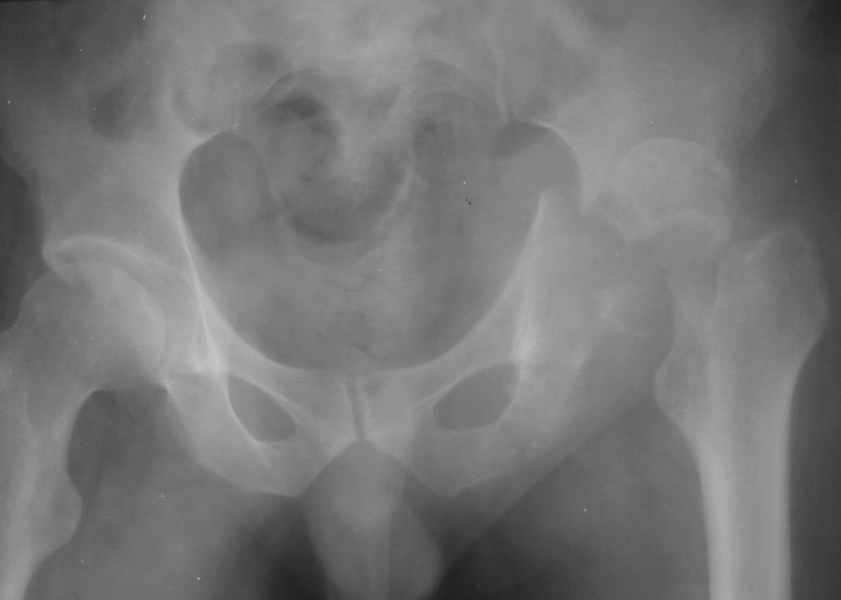

Таз+шейка

Дорогие коллеги, Поступил пациент, 5 месяцев, как сломался.

Поступил для эндопротезирования, но наши корифеи засомневались, не собрать ли сначала таз. Есть ли смысл собирать аппаратом закрыто?